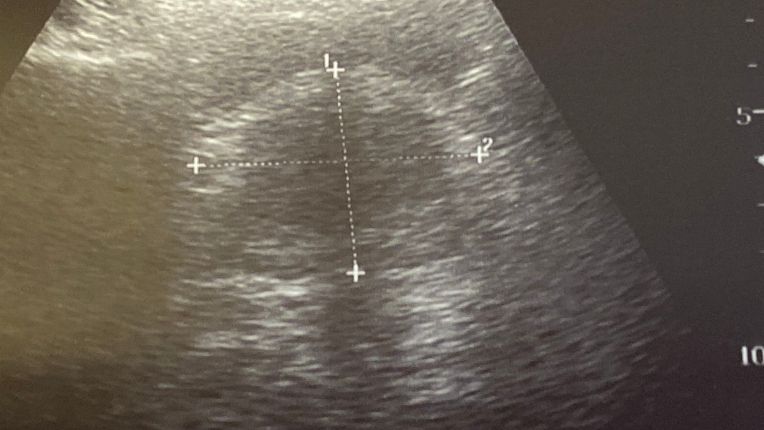

ultrasons,

L’urologie est une spécialité médico-chirurgicale qui concerne les affections de l’appareil urinaire de l’homme et de la femme. Elle touche particulièrement la vessie, l’uretère, l’urètre. Et chez l’homme : la prostate, le pénis et les testicules. Elle s’appuie de plus en plus sur des techniques moins invasives comme :